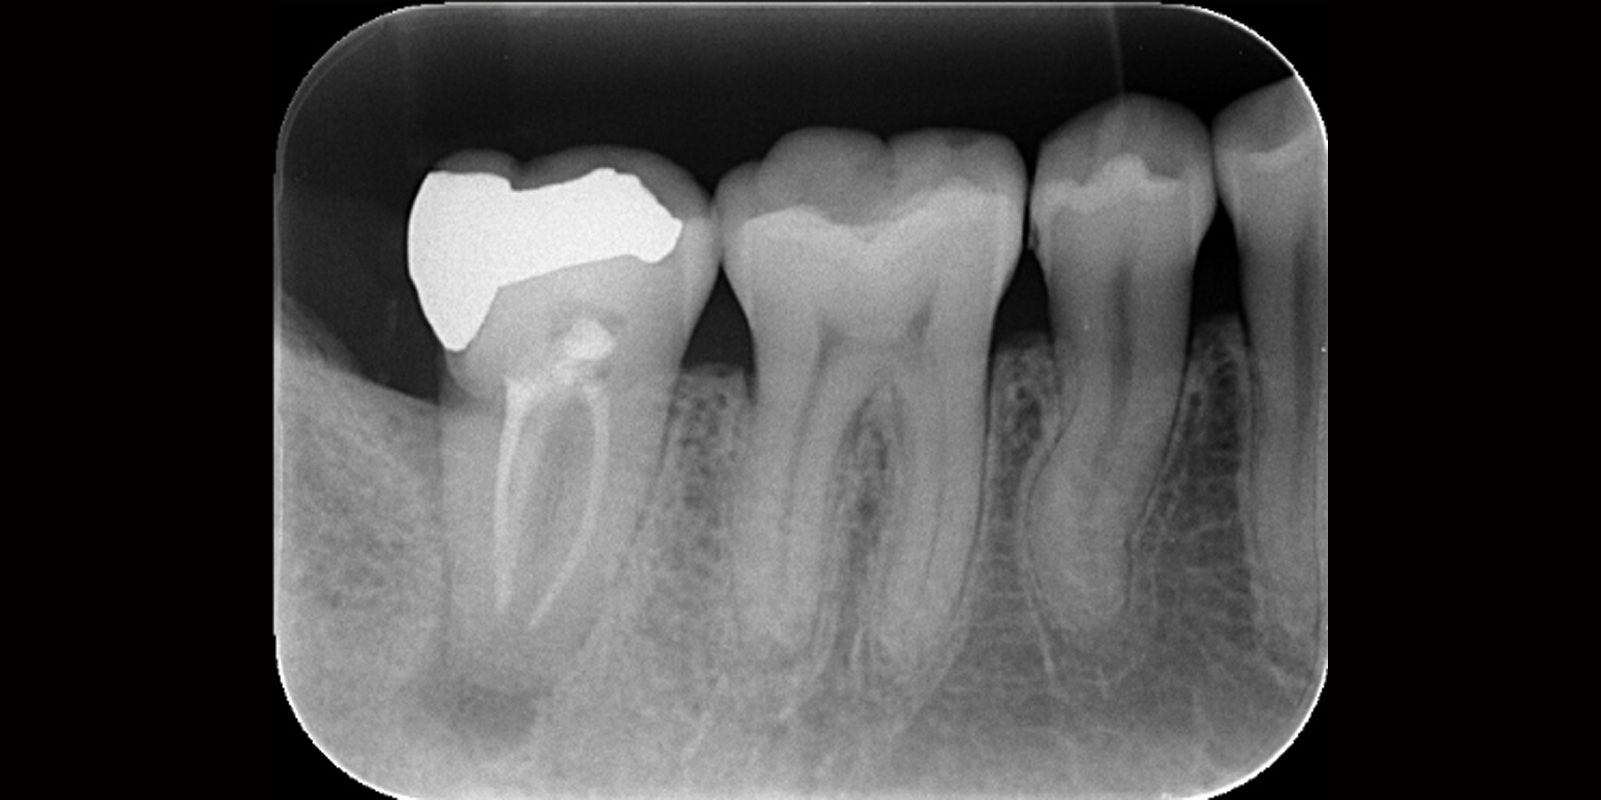

治療前

治療後

主訴 | 他院で抜歯と言われたが、残せないか相談 |

---|---|

治療期間 | 2ヶ月 |

治療費 | 130,000円 |

治療内容 | マイクロスコープを用いた精密根管治療 |

治療のリスク | 歯の状況によっては歯の保存が難しい場合がある |